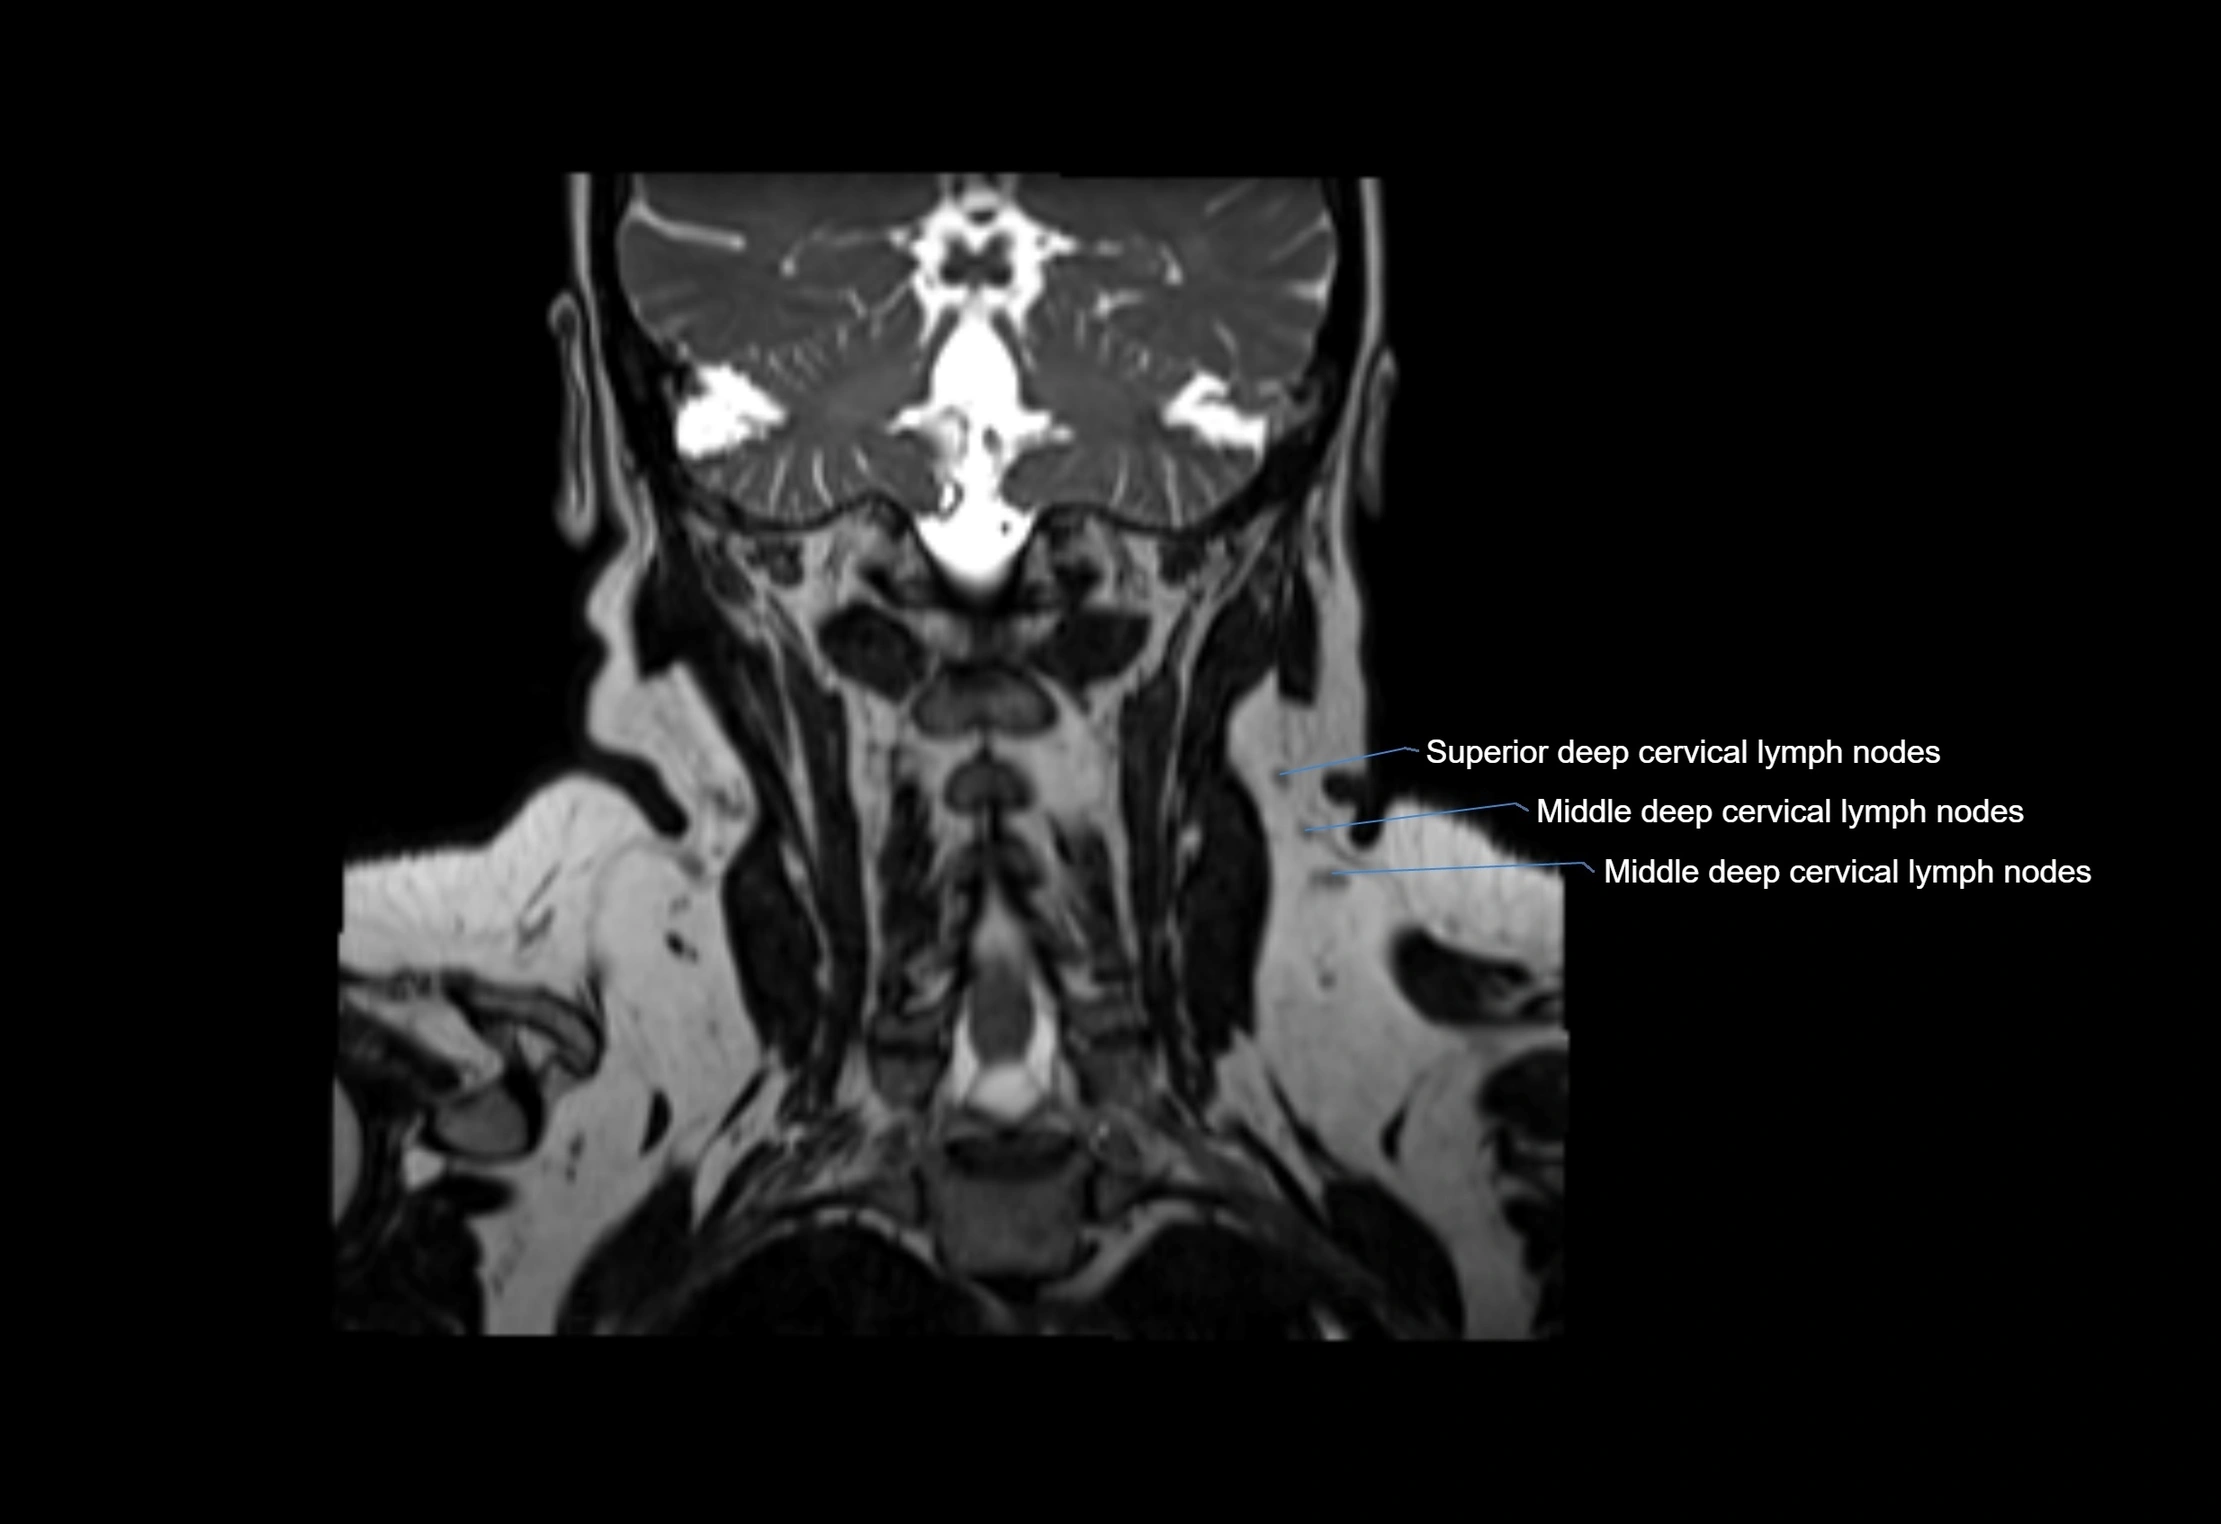

Location

• Found along primary lymph node chains, including preauricular, submandibular, parotid, and occipital regions

• Embedded in subcutaneous fat or superficial fascia, often lateral or posterior to primary nodes

MRI Appearance

T1-weighted images:

• Normal accessory nodes appear as small, oval hypointense to intermediate signal structures within subcutaneous fat

• Surrounded by hyperintense fat, enhancing contrast for visualization

T2-weighted images:

• Nodes show intermediate signal, with surrounding fat bright

• Useful for detecting edema, inflammation, or infiltration

• Fatty hilum may appear slightly hyperintense relative to cortex

MRI images

image